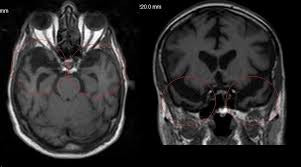

Beyin hücrelerinin yok olmaya başlaması sonucu ortaya çıkan alzheimer bir demans türüdür. İhmal edildiğinde ciddi sağlık sorunlarına neden olan ve günlük hayatı zorlayan alzheimer, bazı sinyaller verir. Alzheimer hastalığının tanısı genellikle ilk belirtilerinden yıllar sonra konulur. Bunun nedeni alzheimer hastalığının çoğu zaman sinsi ilerlemesidir. Peki, alzheimer hastalığının ilk belirtisi nedir? Haberimizin devamını okumak için Lütfen sonraki sayfaya geçiniz..

Yıllar önce bu sinyali veriyor! Alzheimer hastalığı, ilerleyen bir nörolojik bozukluktur ve genellikle yaşlılık döneminde ortaya çıkar. Bu hastalık, bilişsel işlevlerde giderek kötüleşmeye, hafıza kaybına ve günlük yaşam aktivitelerinde zorluklara yol açar. Alzheimer hastalığının belirtileri zamanla artar ve şiddetlenir. İşte Alzheimer hastalığının yaygın belirtileri…

Yıllar önce bu sinyali veriyor! Alzheimer hastalığı, ilerleyen bir nörolojik bozukluktur ve genellikle yaşlılık döneminde ortaya çıkar. Bu hastalık, bilişsel işlevlerde giderek kötüleşmeye, hafıza kaybına ve günlük yaşam aktivitelerinde zorluklara yol açar. Alzheimer hastalığının belirtileri zamanla artar ve şiddetlenir. İşte Alzheimer hastalığının yaygın belirtileri…HAFIZA KAYBI: İlk belirti genellikle teşhisten yıllar önce ortaya çıkar. Alzheimer hastalığının ilk belirtisi; yeni bilgileri öğrenme ve hatırlama yeteneğinde zorluktur. Kişi sık sık nesneleri, yerleri veya önemli tarihleri unutabilir.